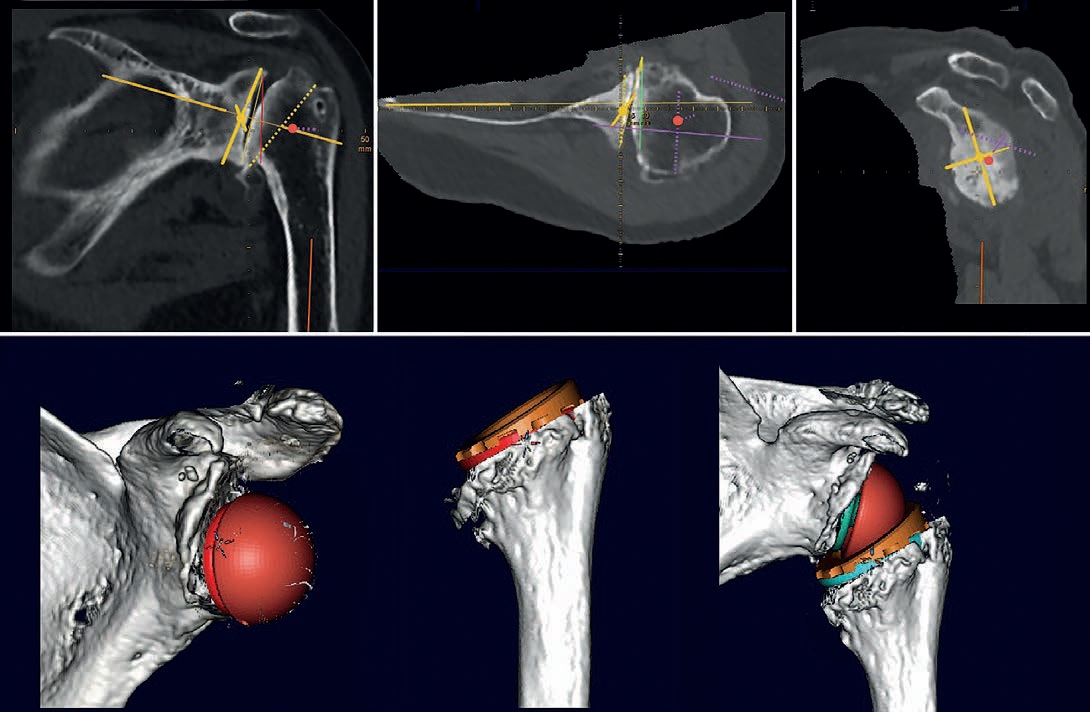

schneller. Ich brauche bspw. zwischen 5 und 10 Minuten für eine normale Schulterplanung. Für eine 3D-Planung

mit einer 3D-Gelenkrekonstruktion inklusive animierter 3D-ROM-Analyse und Betrachtung des Gelenkes aus verschiedenen

Blickwinkeln, so wie es aktuell mit der Software mediCAD® Shoulder 3D ermöglicht wird, brauche ich derzeit noch

ca. 30 Minuten.

Gerade das 3D-reponierte Gelenk, insbesondere bei der inversen Schulter TEP, mit sichtbarer implantierter Prothese

und Betrachtungsmöglichkeit aus jedem Blickwinkel im Raum, ist für mich derzeit noch etwas spannendes Neues mit

vielen noch möglichen Variablen. Derzeit versuche ich diese spielerisch herauszufinden, um die bisher bekannte optimale

Prothesenposition zu finden, anhand neuer Möglichkeiten zu überprüfen und zu validieren, idealerweise unter Berücksichtigung

Die Vorteile einer 3D-Planung

Ich versuche bei jeder anstehenden OP mindestens eine digitale 2D-Planung, idealer Weise sogar eine 3D-Planung zu

machen. 3D-Planungen basieren aber auf CT-Bildern, und leider habe ich nicht immer ein geeignetes CT in der entsprechenden

Dünnschicht-Auflösung und Abmessung (ganzes Schulterblatt und Epicondylen ) zur Verfügung, denn viele Patienten

haben nur ein MRT dabei, bei dem meist nicht die eigentlich erforderlichen Endpunkte der betroffenen Knochen

abbgebildet sind und gehen davon aus, dass dies ausreichend sei. Eine digitale 2D-Planung ist aber auch anhand eines

MRT in Annäherung möglich, allerdings mit deutlich eingeschränkter Aussage gegenüber der 3D Planung mit reproduzierbaren

Referenzebenen in den Schulterblattebenen und Humerusachsen.

Das Schultergelenk besteht wie jedes Gelenk am Körper aus zwei sich gegeneinander bewegenden Gelenkpartnern, die

über Weichteile miteinander verbunden sind und nur bestimmte Größen und Positionen des Gelenkersatzes gewährleisten,

auch nach der OP, die regelrechte, für den Patient zufriedenstellende, langfristige Funktion. Wenn es heute mit der

mediCAD® animierten 3D-Gelenkplanung mit ROM-Analyse präoperativ Möglichkeiten gibt diese optimalen Prothesengrößen

und deren Ausrichtung zu simulieren, inklusive der aus knöchernen und implantattechnischen Gesichtspunkten

möglichen technischen Bewegungsfreiheit, gibt es für mich nichts Naheliegenderes als dies ohne OP-Risiko in Ruhe

vorab zu simulieren und auszutesten. Dann kann ich entspannt und mit klarem Konzept sowie gutem Gewissen dem

Patienten gegenüber in die Operation gehen.

Weiterer Vorteil von von mediCAD® Shoulder 3D ist, dass der Operateur mit der Software selbst (und nicht irgendein

Ingenieur des Implantatherstellers) die Segmentierung des CT-Datensatzes durchführen kann, entsprechend seiner medizinischen

Erfahrung und Interpretation der CT Bilder. Außerdem sind das Erstellen eines 3D-Modells und die Möglichkeit

der anschließende Planung von Glenoid und Humerus einzeln hintereinander möglich. Auch die vollständige

Gelenkplanung nach der Reposition des Gelenkes mit implantierten Komponenten sind Funktionen, die ich als Arzt nicht

missen möchte. Und natürlich die 3D-ROM-Analyse des reponierten Gelenkes bei innenliegender Prothese.